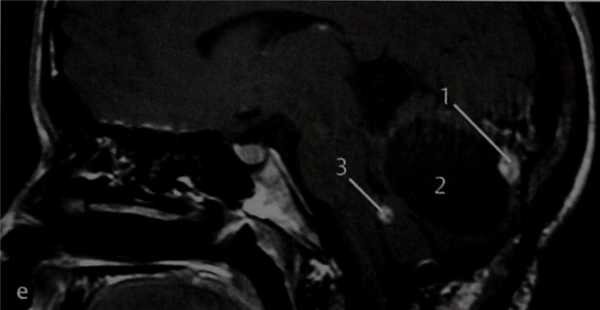

КТ в горизонтальной проекции. Видна деструкция заднемедиального отдела височной кости в области предполагаемого расположения эндолимфатического мешка, по-видимому, обусловленная его опухолью. Водопровод преддверия при этой опухоли может быть расширен (1), и в большинстве случаев опухоль прорастает в окружающую ее кость (2), распространяясь на луковицу ВЯВ, внутренний слуховой проход, сосцевидный отросток, внутреннее ухо. Поражение интракраниальных структур лучше видно на МРТ.

КТ в вертикальной проекции. Наиболее крупная часть опухоли (1) локализуется в крыше луковицы ВЯВ (2) и частично инфильтрирует медиальные сосцевидные ячейки вплоть до средней черепной ямки. Видны шилососцевидное отверстие (3) и задний полукружный канал (4). Как и в данном случае, опухоль эндолимфатического мешка чаще образуется при болезни Гиппеля-Линдау, а вообще эта опухоль встречается редко.

МРТ: Т2-взвешенное изображение в горизонтальной проекции. Опухоли на МРТ соответствует зона повышенной интенсивности сигнала в заднемедиальной части височной кости (1) кзади от заднего полукружного канала с нормальным сигналом от содержащейся в нем жидкости, что подтверждает результат КТ.

d МРТ: Т1 -взвешенное изображение в горизонтальной проекции после введения препарата гадолиния. Видно значительное усиление сигнала от опухоли, располагающейся слева (2), что подтверждают ее гиперваскуляр-ность, а также нормальный кровоток в обоих сигмовидных синусах (3).

МРТ: Т1-взвешенное изображение в сагиттальной проекции после введения препарата гадолиния. При болезни Гиппеля-Линдау могут возникать и другие опухоли, что значительно усугубляет состояние пациентов, учитывая возможность сдавления этими опухолями жизненно важных анатомических структур и развития вторичной гидроцефалии. В данном случае развилась гемангиобластома с усиливающимся солидным (7) и неусили-вающимся крупным кистозным (2) компонентами. Опухоль значительно сдавливает мозжечок. Несколько кпереди визуализируются мелкие вторичные усиленные опухоли (3).